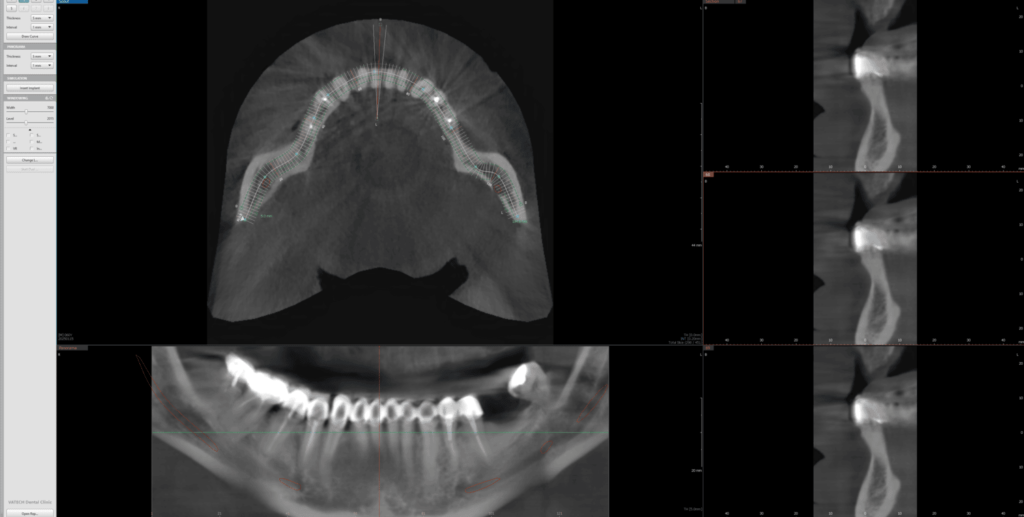

3D/CBCT (kompjuterizovana tomografija sa konusnim snopom) je napredni postupak snimanja u stomatološkoj radiologiji. Koristeći tehnologiju sličnu onoj kod standardnih medicinskih skenera, ali sa drastično smanjenom količinom zračenja, ova metoda pruža izuzetno precizne slike dentalnih struktura. 3D/CBCT omogućava pravljenje detaljnih trodimenzionalnih snimaka koji daju stomatologu potpuni uvid u zubne i koštane strukture, bez skrivenih ili iskrivljenih delova.

2D snimci su uobičajena vrsta snimanja koja prikazuje zube i vilice u jednoj ravni. To uključuje snimke pojedinačnih zuba, ortopane i slično. Za razliku od tradicionalnih 2D snimaka, 3D snimci zadržavaju pravilan odnos struktura, predstavljajući visinu, dužinu i širinu svih struktura u pravom odnosu 1:1.

Ova vrsta snimanja je posebno korisna za kompleksnije dentalne procedure, kao što su oralno-hirurške intervencije, postavljanje dentalnih implanata, ili tretman zuba sa višestrukim korenovima. Zahvaljujući 3D/CBCT snimcima, stomatolozi mogu precizno planirati i sprovoditi ove intervencije.

Važno je naglasiti da, iako 3D/CBCT koristi zračenje, količina emitovanog zračenja je značajno manja u poređenju sa tradicionalnim medicinskim skenerima. Ovo je postignuto kroz upotrebu konusnog snopa zračenja, koji redukuje izloženost pacijenta zračenju